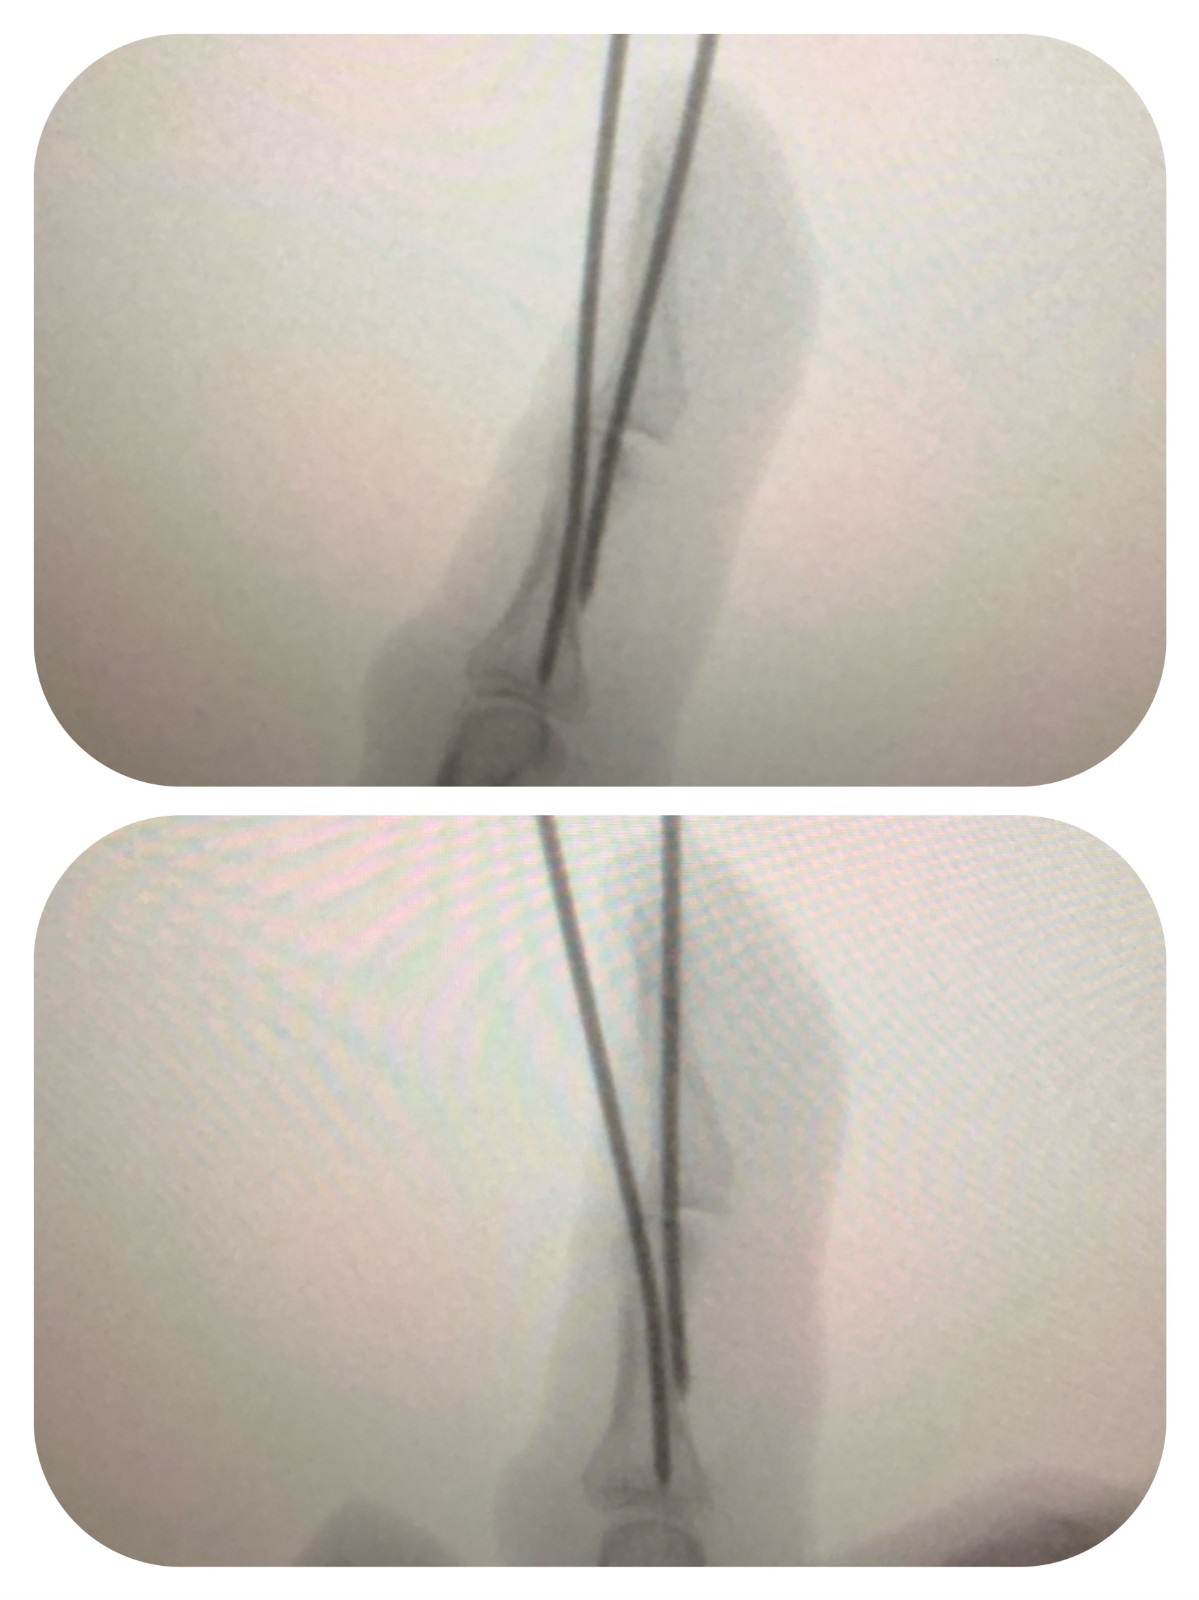

该患者因小指外伤导致典型锤状指畸形,术前X线片显示,小指远节指间关节屈曲,伴随体积微小的撕脱骨块。此类细小骨块质地脆、把持力差,常规穿针固定难以实现精准复位与稳定固定,手术难度较高。

针对患者的特殊伤情,团队最终选择石黑法微创撬拨复位技术,手术在透视引导下精准完成。依托科室一日病房的高效管理模式,患者从术前评估、手术实施到术后观察、康复指导,全流程无缝衔接。